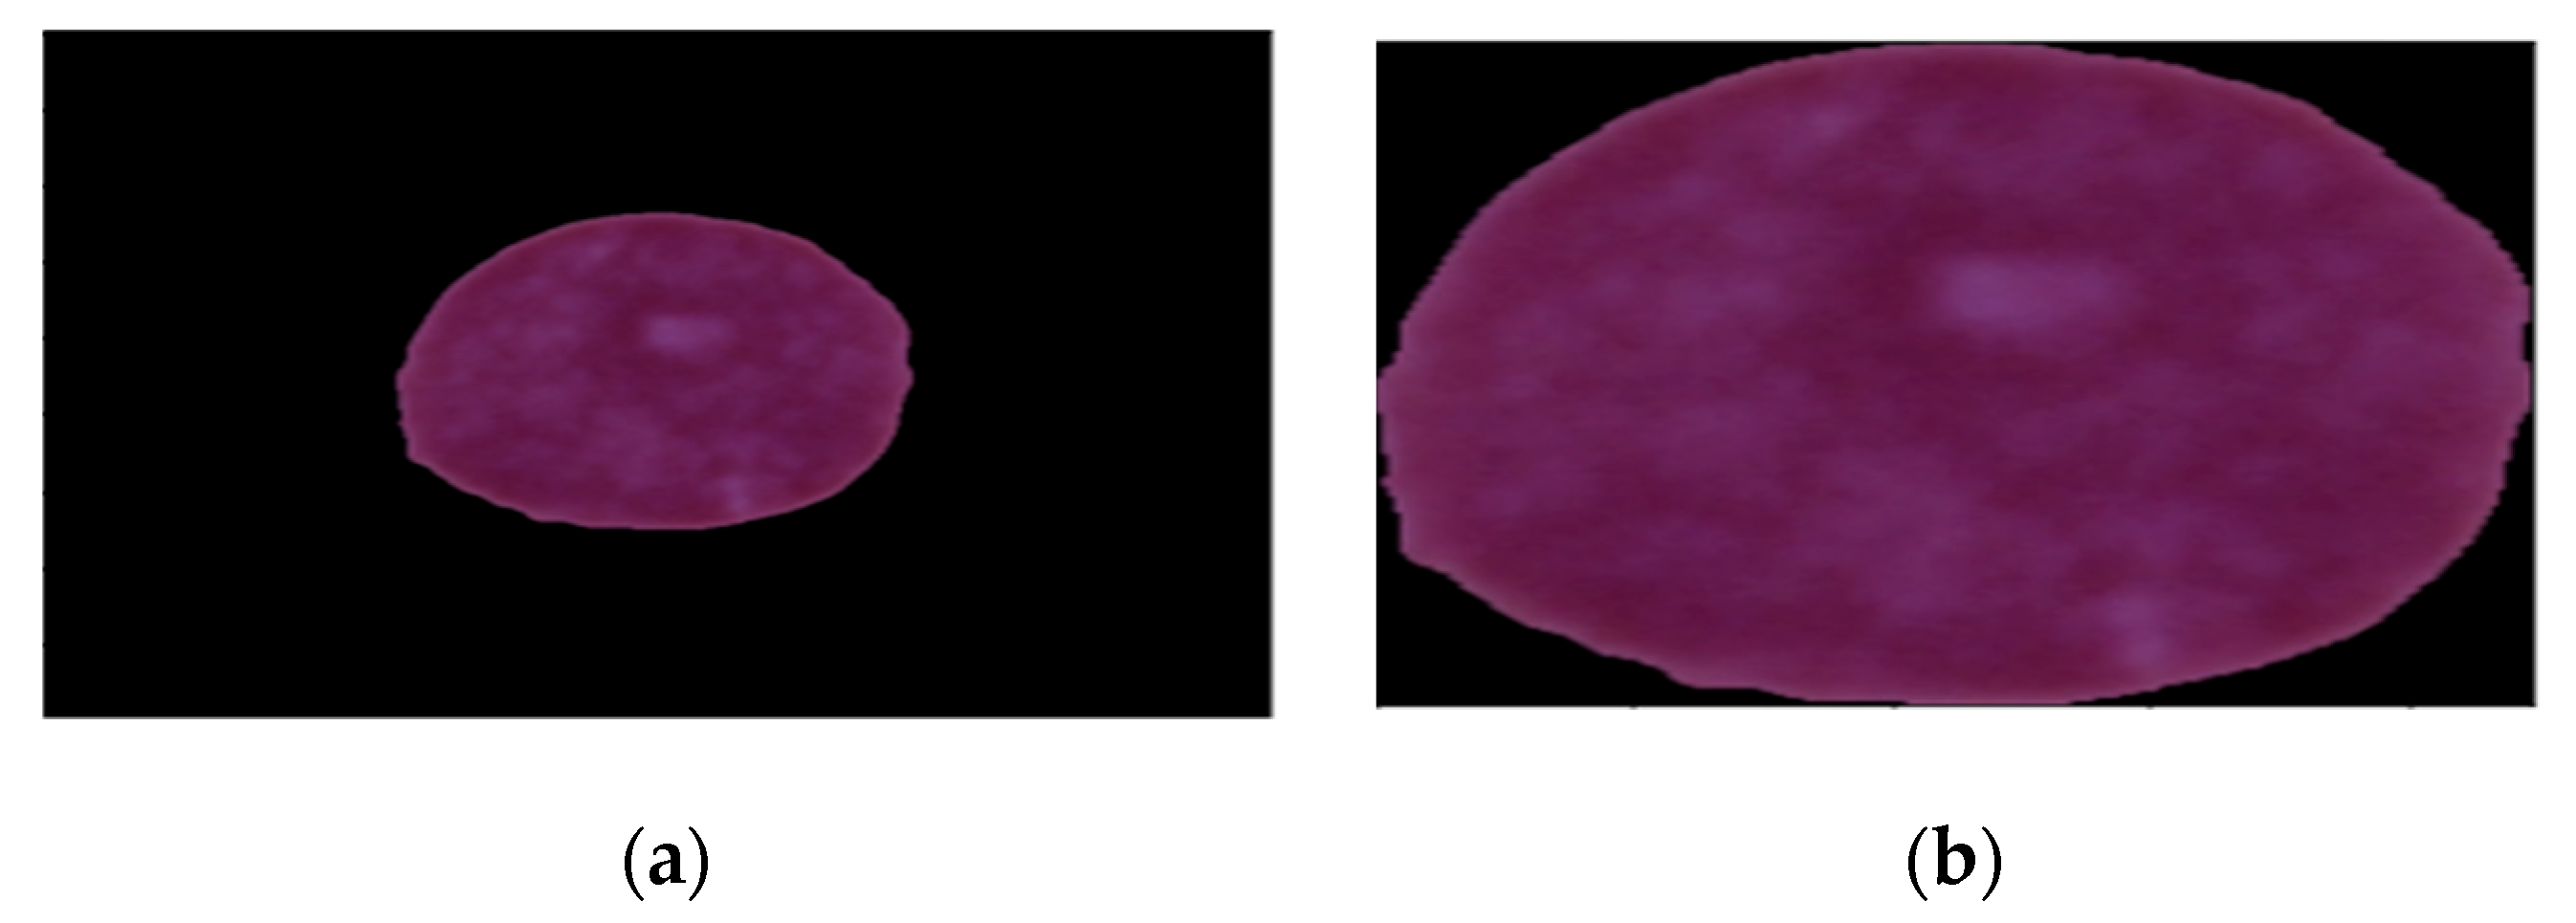

3.2.1. Cropping Black Edges in Images

Cropping black edges in images can be completed using various image processing techniques. The first step involves the conversion of the images to grayscale images. This step makes the detection of edges easier because the images are reduced to a single channel. The next step is to detect the edges of the images. The final step is cropping the image using the coordinates of the bounding box. This is done using the OpenCV’s crop function. Hence, automatic cropping of the black edges present in an image can be carried out using these steps. Figure 3a shows the image before cropping and (b) shows the image after cropping.

Figure 3. Sample images. (a) Before cropping. (b) After cropping.